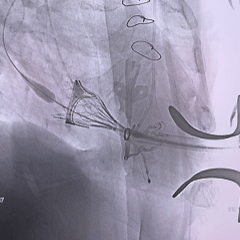

术中影像

右侧垫肩,基本打平原外科瓣瓣架,工作体位:RAO29° CRA12°

直头导丝顺利跨瓣

Mark点平齐外科瓣瓣架低端进行定位

瓣膜全展开位可见同轴稍差,心房内上浅下深

瓣膜回收后,旋转输送器弯型调整同轴

瓣膜重新释放至全展开位,可见位置合适,流出端可见形态压缩

超声评估瓣膜位置可,无瓣周漏

瓣膜稳定脱钩

28mm球囊后扩,瓣膜形态明显改善

最终评估可见瓣膜形态、位置均理想